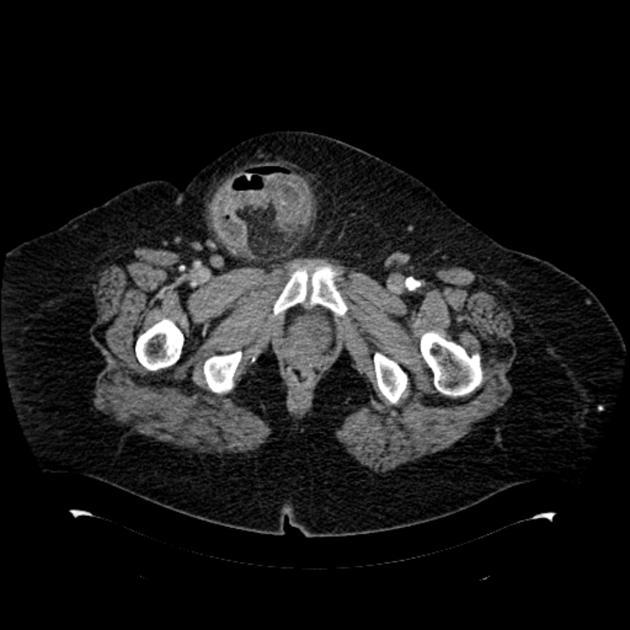

Le patient a une diverticulite. Devant persitance fièvre et augmentation du sd inflammatoire à 48h on réalise le TDM suivant. Vu la taille de l’abcès (>5 cm on va dire), quelle CAT?

drainage de l’abcès: ponction percutanée écho ou scanno-guidée; OU drainage chirurgical si percut impossible (avec RDC à distance)